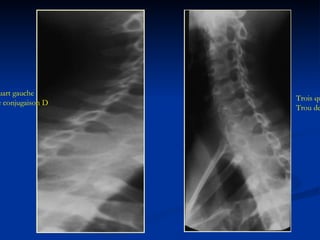

Trois quart droit Trou de conjugaison G Trois quart gauche Trou de conjugaison D

Résultat: Trous deconjugaison tous dégagés et limités par: En haut et en bas par les pédicules. En avant par les coins postéro-latéraux des corps vertébraux, les uncus et les disques. En arrière par les apophyses articulaires .

Trois quart droitTrou de conjugaison G Trois quart gauche Trou de conjugaison D